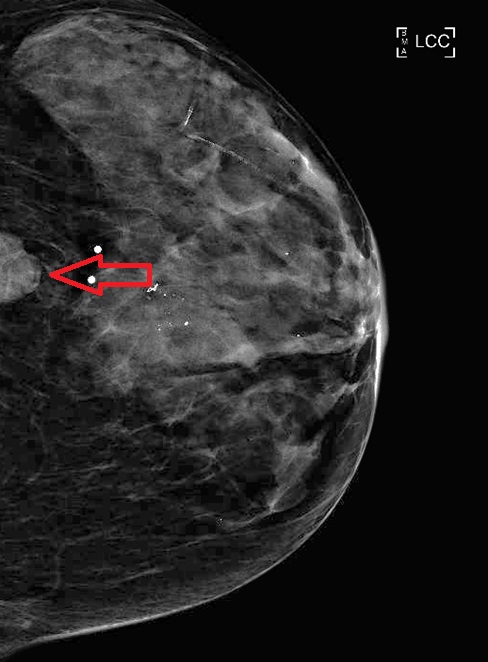

الحالة الأولى: تم اكتشاف كتلة في الثدي الأيسر. ثم تشخيصها بعد عمل خزعة بالأشعة التلفزيونية. تم عمل PET CT بعد ذلك واتضح وجود الكتلة وانتشار لأحد فقرات الظهر. ثم عمل ال MRI ويتضح وجود الكتلة في الجزء الخلفي الخارجي للثدي الأيسر.

تم علاج المريضة بعلاج اشعاعي لمنطقة الفقرة المصابة وعلاج السرطان بالعلاج الكيماوي واختفى بعد ذلك في الرنين المغناطيسي ثم تم استئصاله كاملا والحمدلله.

الحالة الأخيرة: كتلة صغيرة جدا في الثدي الأيسر. تم عمل رنين مغناطيسي واكتشاف انتشار للغدد اللمفاوية المجاورة. تم علاج المريضة واستئصال الكتلة والغدد بشكل كامل.